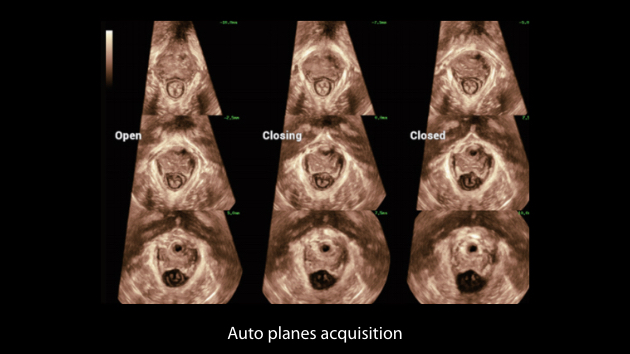

El sistema Nuewa I9, dise?ado exclusivamente para la atenciĂłn mĂ©dica neonatal y de mujeres, brinda una experiencia innovadora integral. Estas innovaciones se desarrollan sobre la base de un conocimiento profundo de situaciones clĂnicas complejas para proporcionar respuestas precisas y oportunas, una gran eficiencia y una experiencia de usuario extraordinaria.

La plataforma ZST+?es una innovaciĂłn extraordinaria que representa toda una evoluciĂłn en el ĂĄmbito de la ecografĂa. Transforma las mĂ©tricas ecogrĂĄficas de la formaciĂłn de haces convencional al procesamiento basado en datos de canal. Supera la limitaciĂłn tradicional de tener que equilibrar entre resoluciĂłn espacial, resoluciĂłn temporal y uniformidad del tejido, con lo que ofrece una calidad de imagen excepcional para soluciones de producciĂłn de imĂĄgenes infinitas con mejoras continuas.